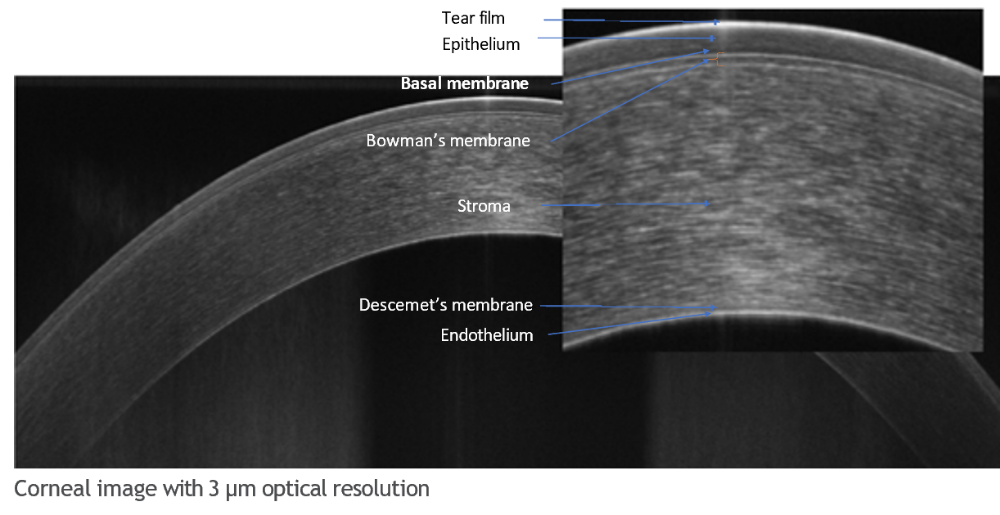

- Topographie OCT : le module Topographie OCT fournit l'analyse des deux surfaces en fonction de la courbure cornéenne, de la puissance dioptrique, de l'élévation et de l'analyse de la puissance réelle en fonction des surfaces et de l'épaisseur locale de la cornée (Ray tracing).